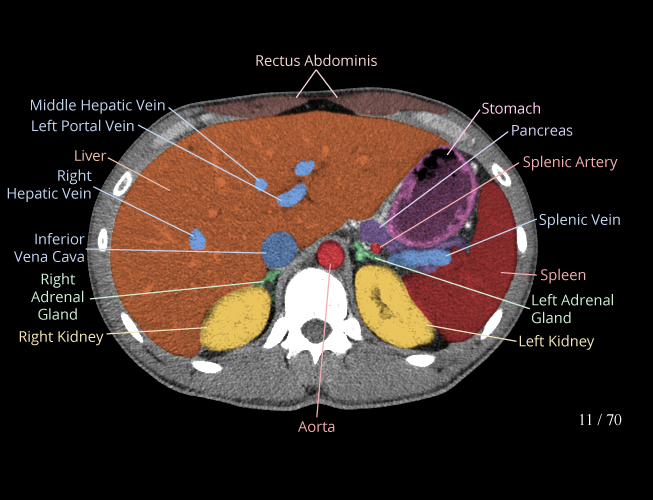

Body

Covers abdominal CT anatomy.